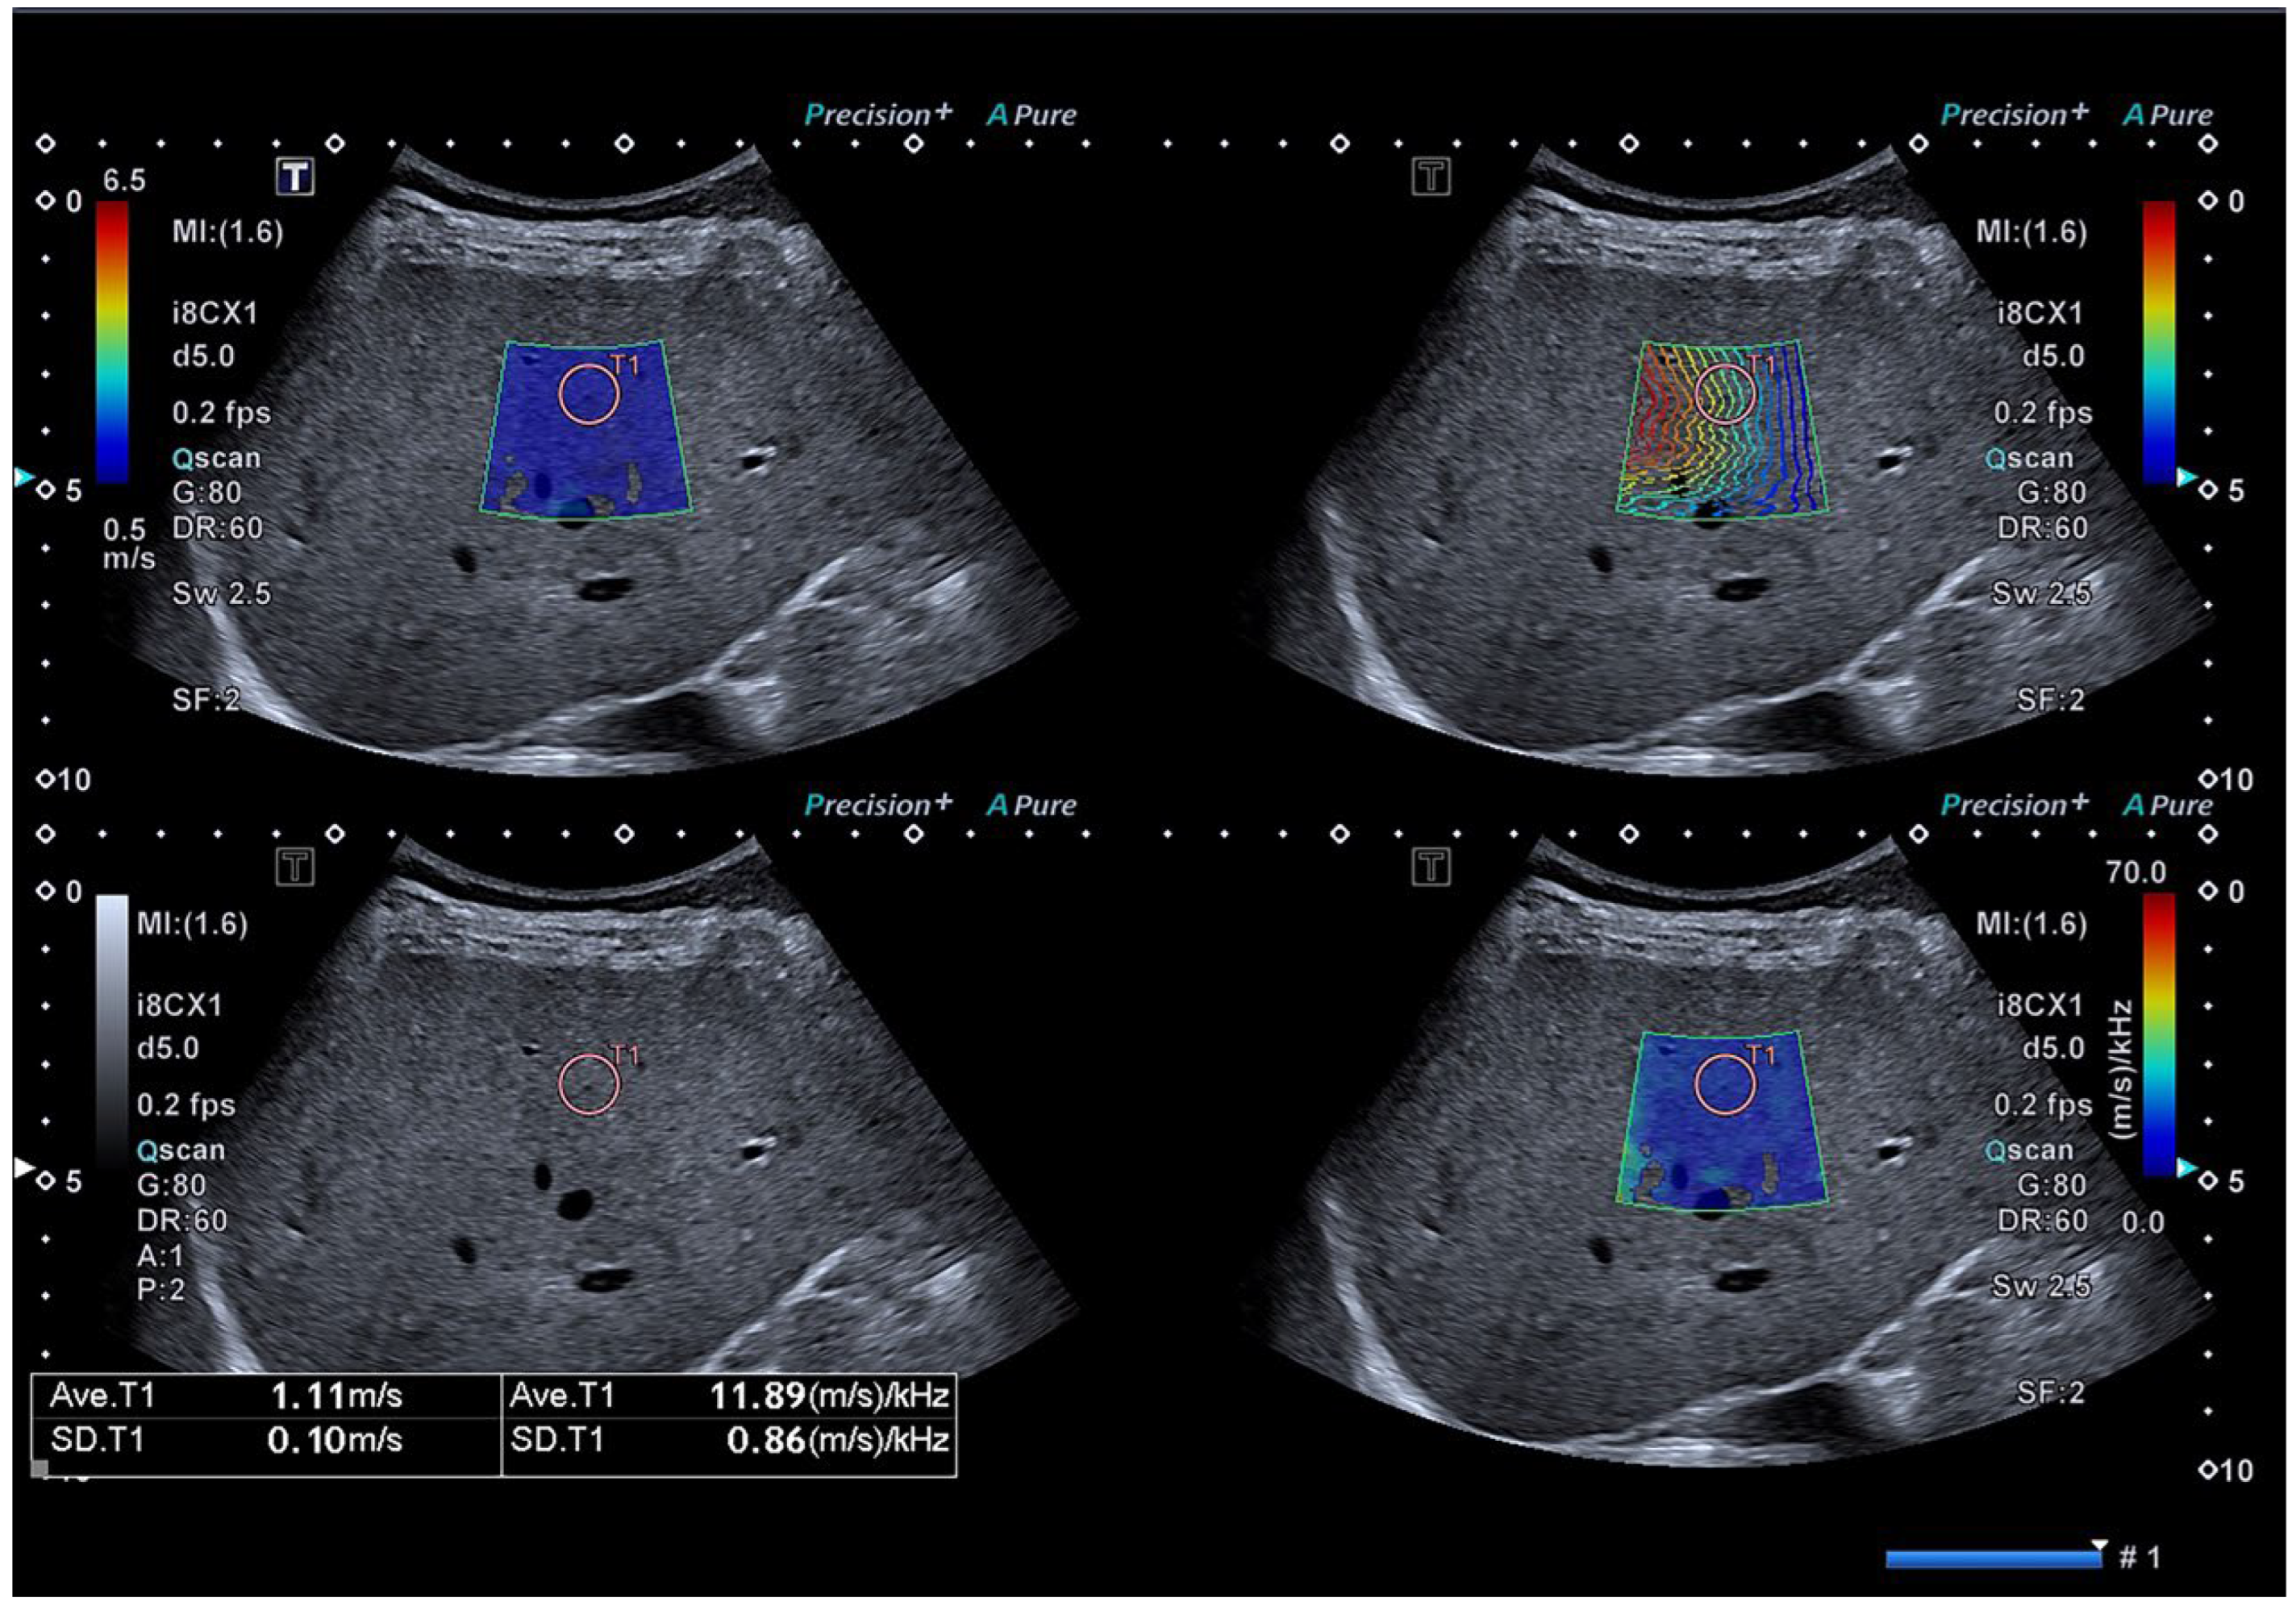

Figure 2.

Representative image of the SWD/SWS examination. A shear wave elasticity map is on the upper left, shear wave propagation map is on the upper right, normal US image is on the lower left and shear wave dispersion map is on the lower right. A 10 mm circular ROI is placed in the liver parenchyma free of large hepatic vessels under the guidance of the propagation map. A shear wave speed (SWS) value of 1.11 m/s and shear wave dispersion (SWD) value of 11.89 (m/s)/kHz are shown at the bottom of image.